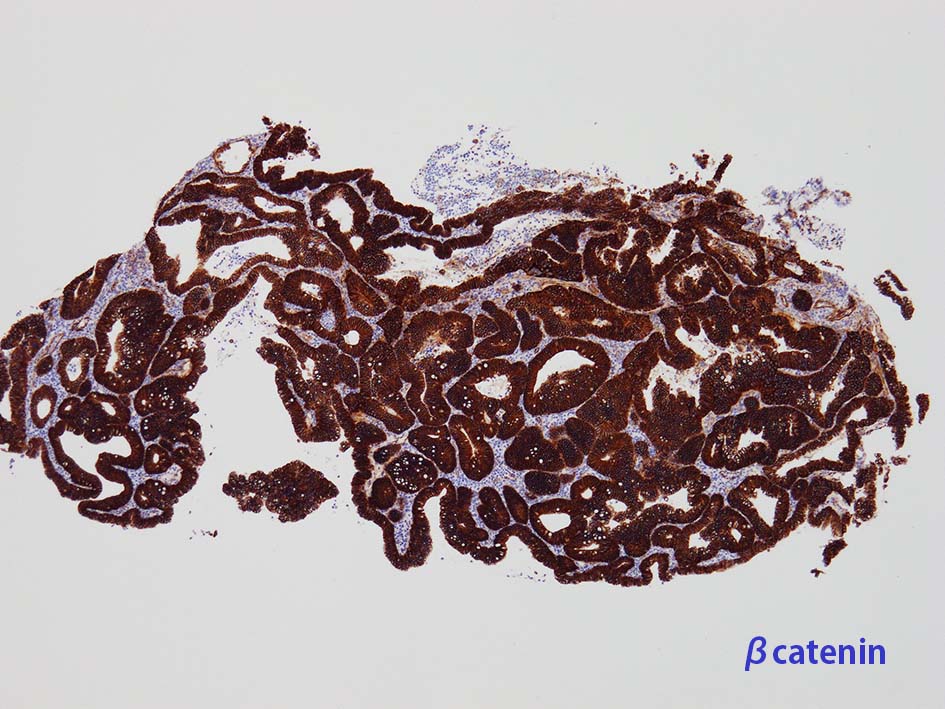

膀胱原発腺癌の診断に, サイトケラチン7および20、34βE12、トロンボモジュリン、CDX2およびβカテニンなどの免疫組織化学的パネルが提案されている。しかし他の原発部位に発生する腺癌と組織像だけでなく免疫組織化学的特徴が重複している. 原発性腺癌と転移性腺癌では予後や治療法が大きく異なるため, 鑑別診断において膀胱腺癌の診断を下す際には、臨床的、画像的、組織的、および免疫組織化学的な相関を注意深く確認する必要がある。

mark-g.gif 免疫染色

GI tract, とくに大腸癌の膀胱浸潤/転移を最初に考えた.